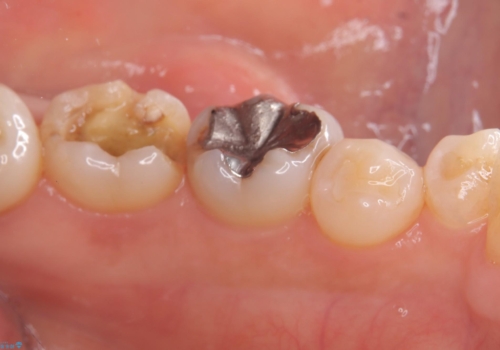

- 主訴:詰め物が外れた これを機に白い詰め物にやり替えたい

左下7番目の歯の詰め物が外れ、セラミックインレーでのやり替えとなりました。

隣在歯にも保険適用もメタルインレーが入っており、咬合面のインレーと歯質の境目が虫歯になっていたこともあり、合わせてのやり替えとなりました。

左下7番めの歯、フロスを通したらインレーが外れてしまったとのことで、適合具合の精密さや、これを機に白い詰め物にしたいとのことからセラミックインレーでのやり替えとなりました。

また、6番目の歯にも保険適用のメタルインレーが入っており、咬合面インレーと歯質境目にう蝕を認め合わせてのやり替えとなりました。